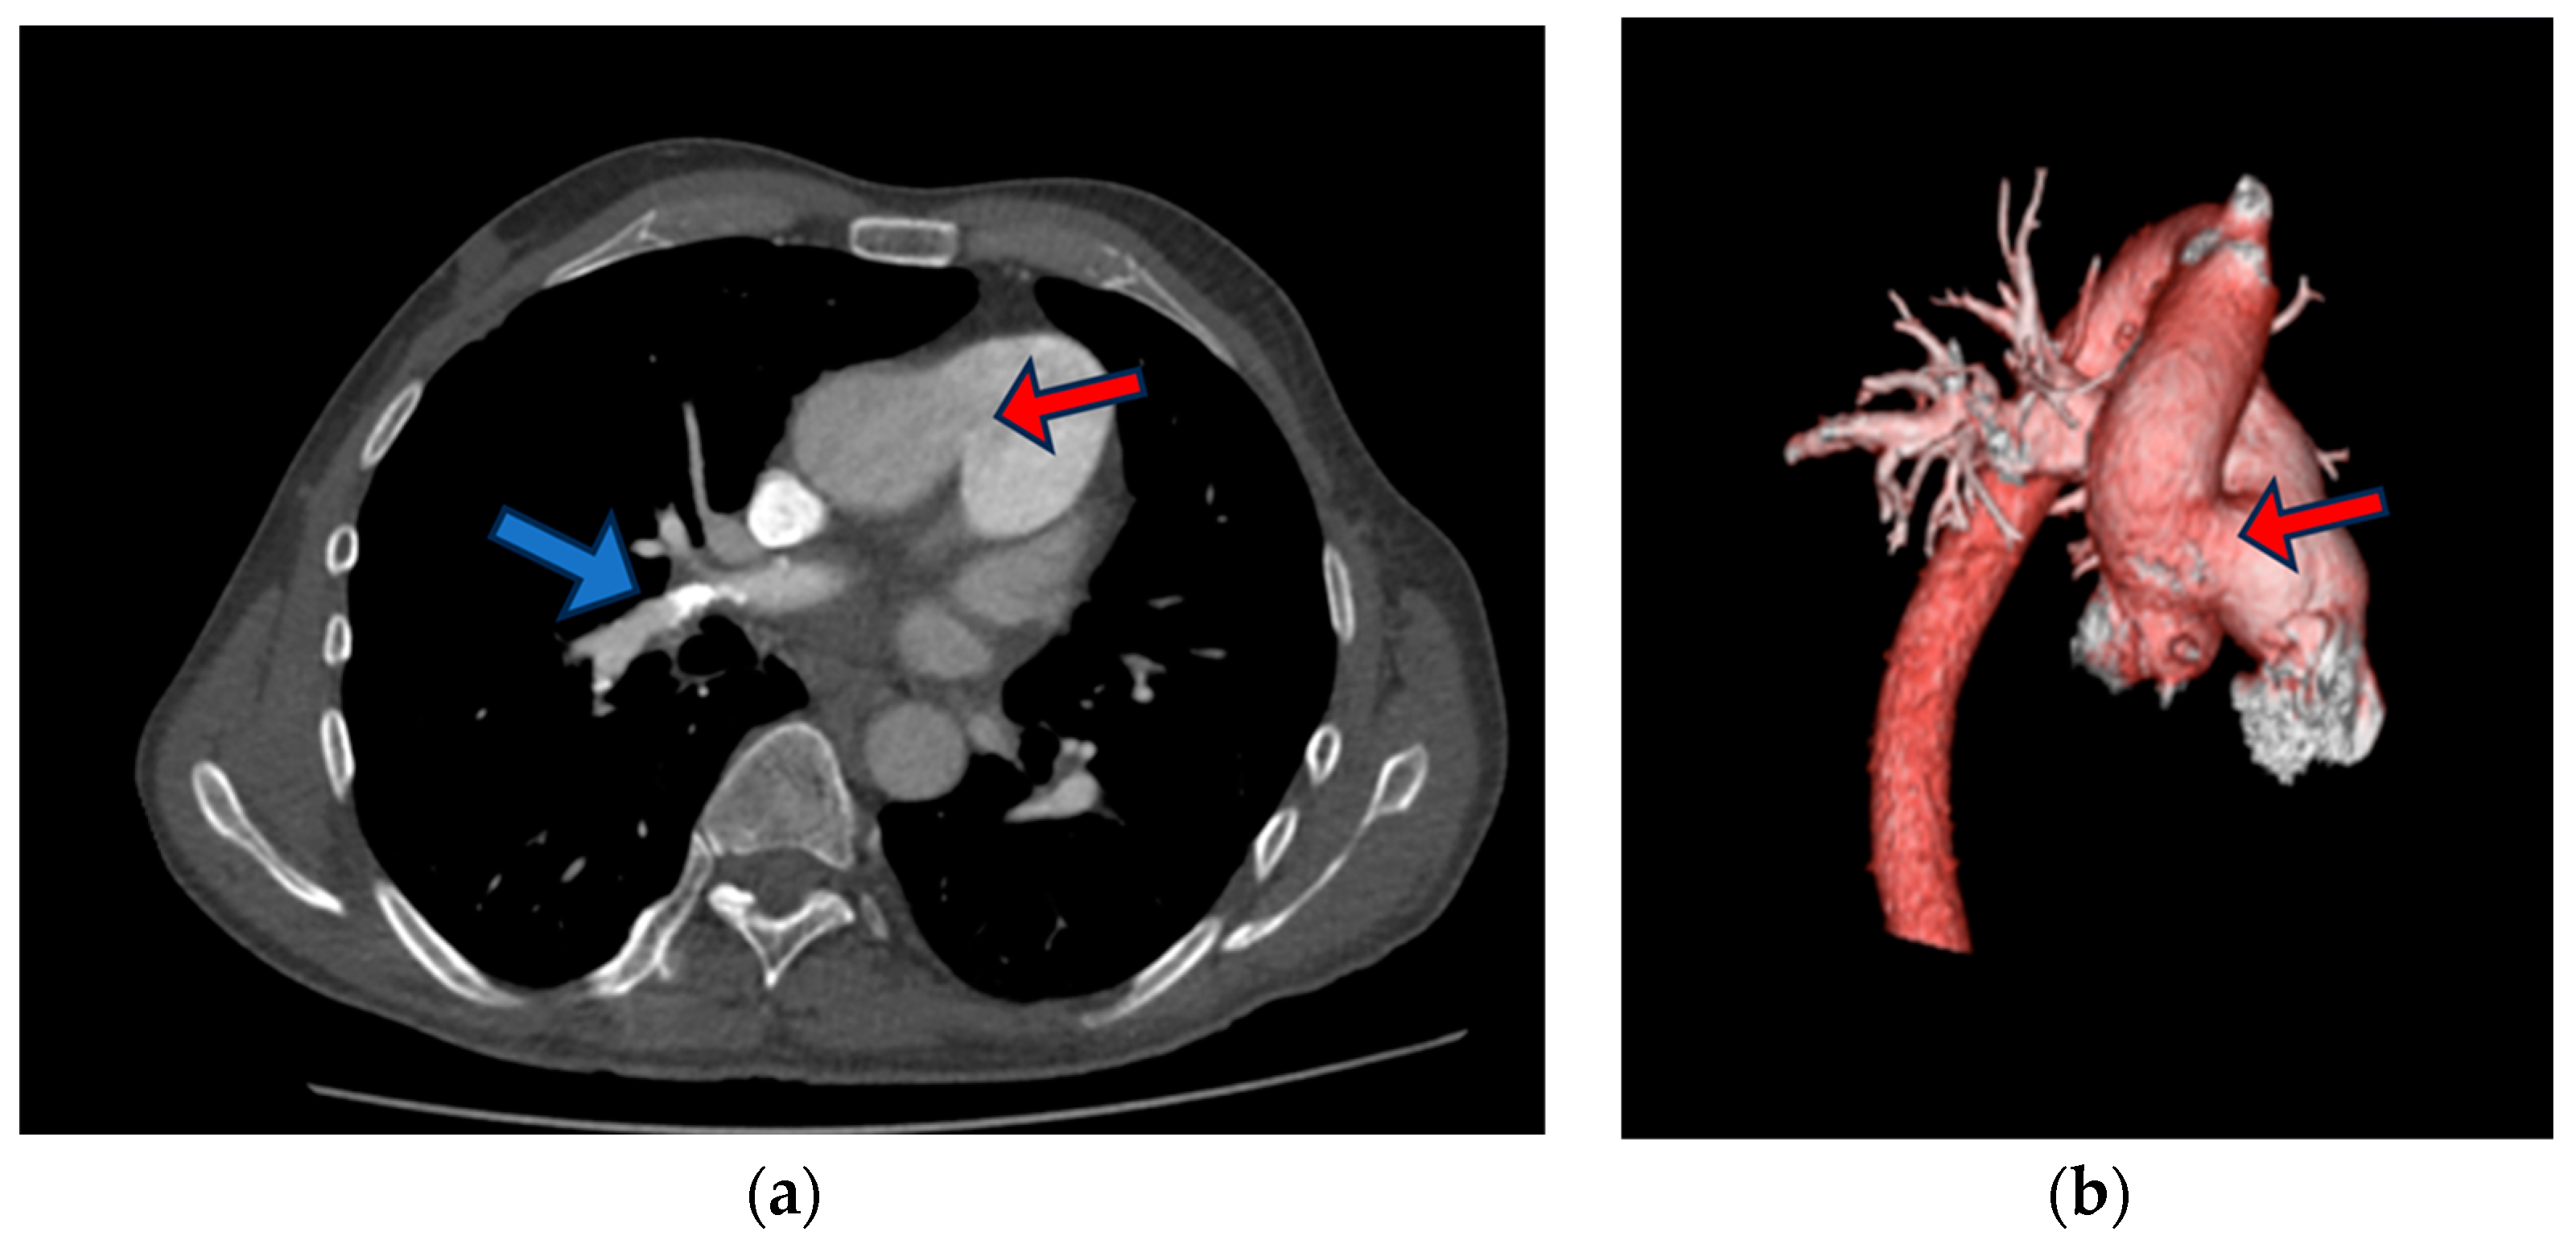

At the pulmonology clinic, an urgent chest computed tomography angiography CTA was performed following the PE protocol. The results revealed insufficient data for an acute PE, showing only signs of pulmonary hypertension, including RV dilatation, RV hypertrophy, and a dilated pulmonary trunk (diameter 37 mm). However, in several right upper lobe anterior segment sub-segmental branches, small filling defects with adjacent calcification were identified—indicative of chronic PE. The size of the defect between the aorta and the proximal part of the pulmonary trunk measured up to ~3.2 cm (Figure 3).

Figure 3. Chest CT (a) slide that shows aortopulmonic window (red arrow), right upper lobe anterior segment sub-segmental branches with small filling defects with adjacent calcification (blue arrow), (b) three-dimensional (3D) reconstruction of contrast-enhanced CT angiography images of the thoracic aorta and pulmonary artery trunk showing aortopulmonic window (red arrow).